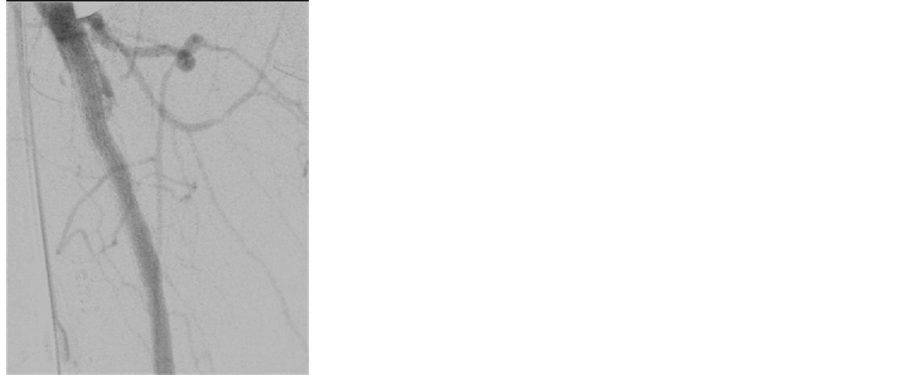

Endoprosthesis, expanded polytetrafluoroethylene (ePTFE) liner attached to an external nitinol stent) was then deployed in the proximal SFA, under direct supervision, without the aid of fluoroscopy. The proximal end of the stent is positioned to be deployed at the distal end of the arteriotomy (Figure 3). After completion of the endarterectomy (Figure 4), a Bovine pericardium patch was then used to repair the arteriotomy (Figure 5). A completion arteriogram was then performed in cases where fluoroscopy was needed for treatment of other lesions (Figure 6).

Figure 6. Completion arteriogram.